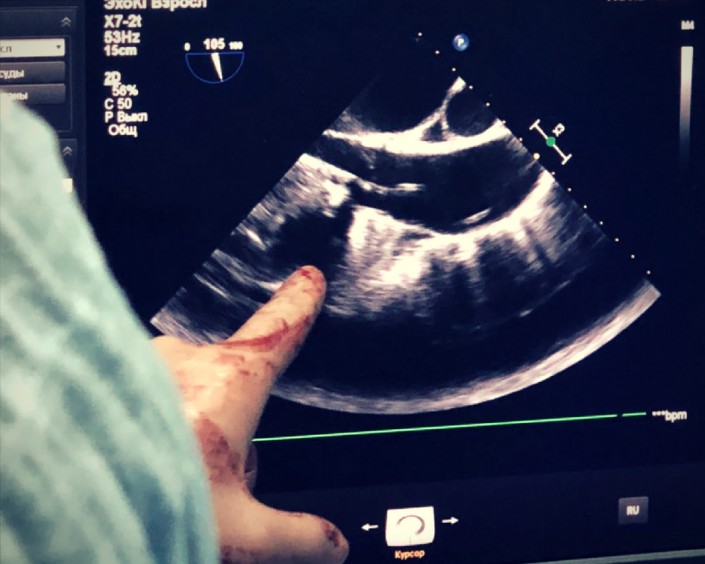

Снова делаем снимки и через рентген проверяем, как действует наша установка.

Важный момент: вся операция проводится на работающем сердце, без аппарата искусственного кровоснабжения, в отличие от манипуляции на открытом сердце. Таким образом, нам не приходится его остановливать и рисковать, что в случае с пожилыми пациентами особенно опасно.